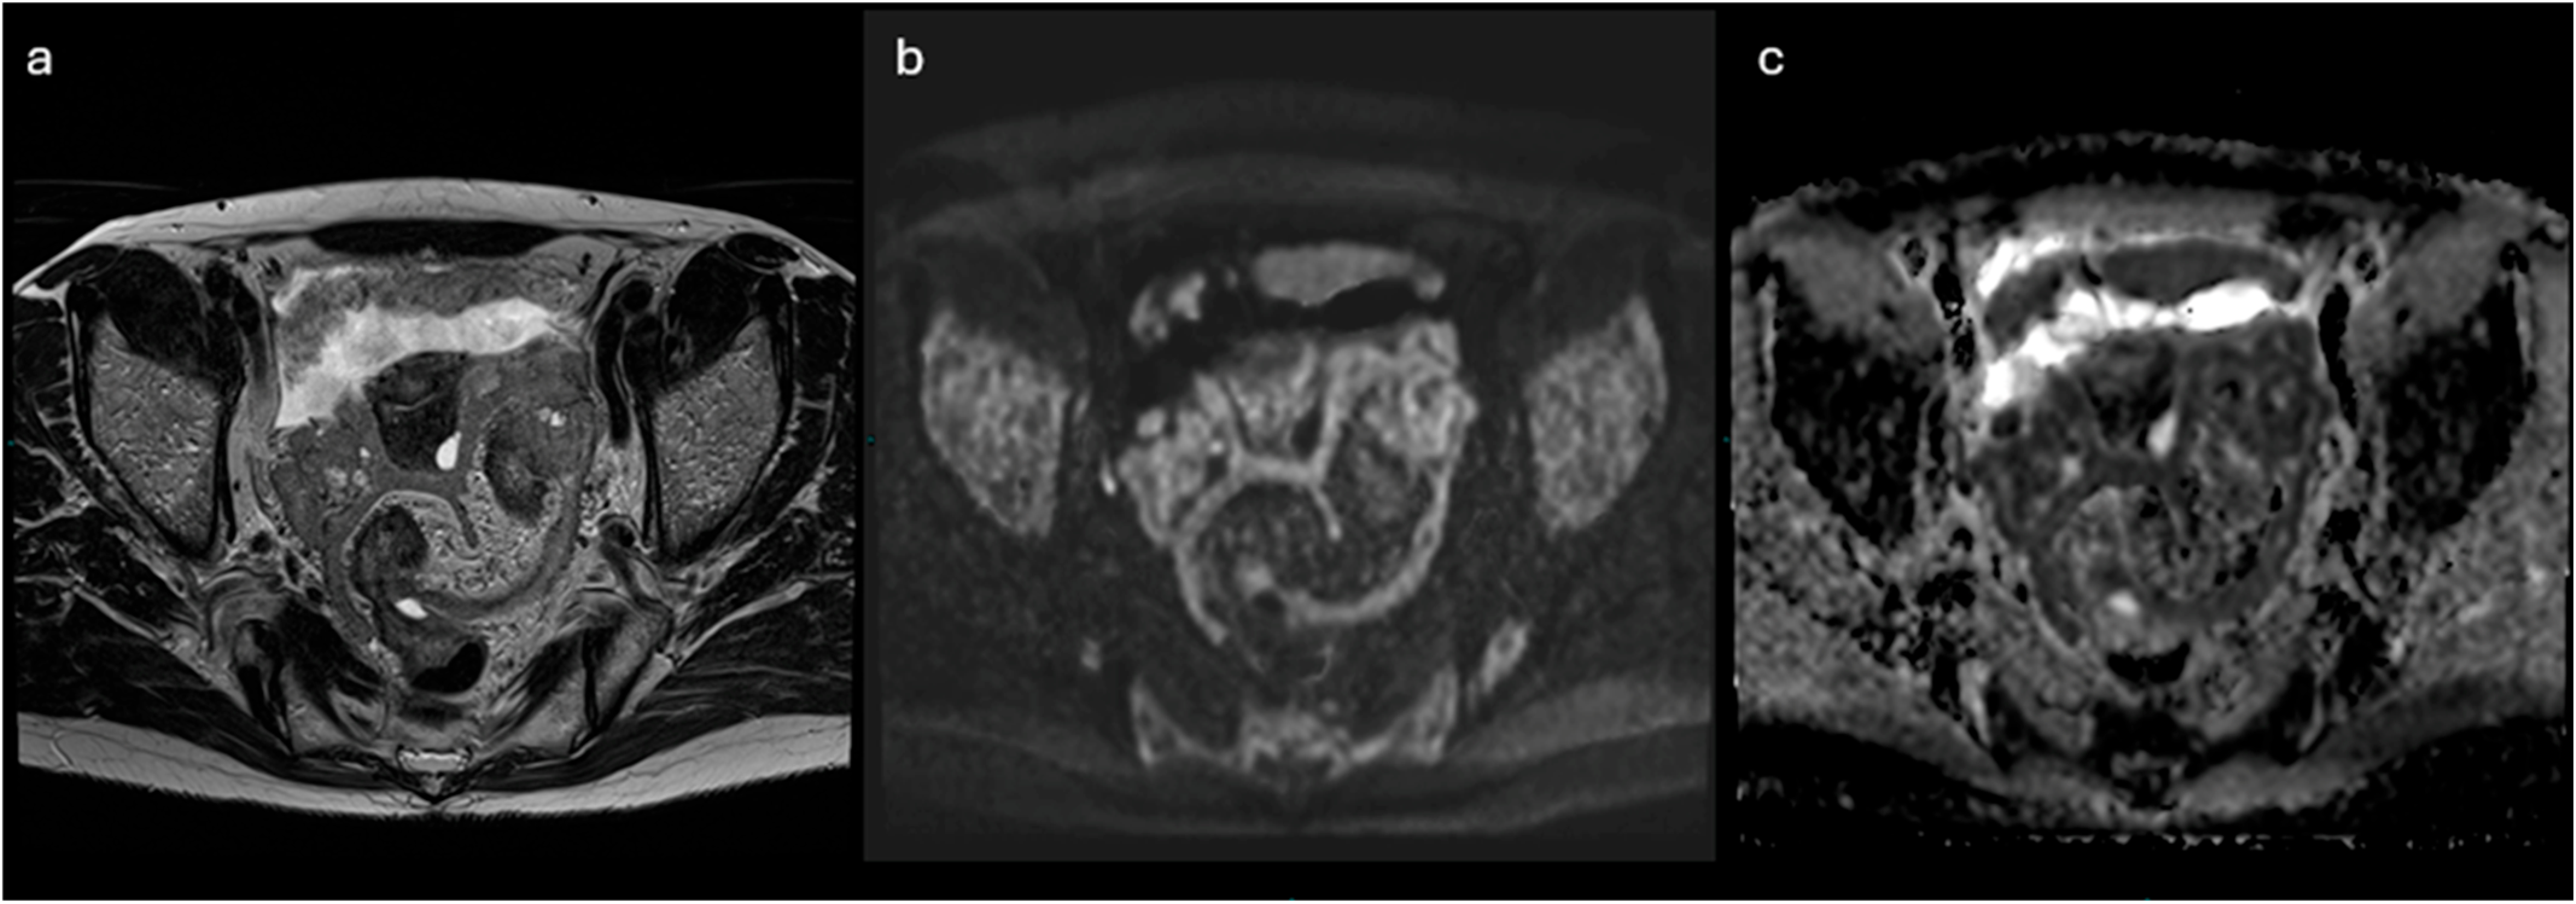

2.3. MRI

2.3.1. ADNEX-MR Scoring System

- Lesions with solid tissue (excluding solid lesions described in score 2) showing type 2 enhancement curve (intermediate risk; Figure 5)

- Solid lesions showing enhancement < myometrial at 30–40 s, if perfusion study is not available